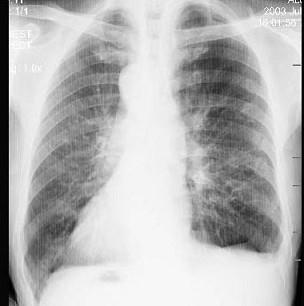

问题 男,68岁,因左胸部外伤摄胸片,根据常规胸片所示,选择下述正确的答案 ( )

选项 A、右肺占位 B、右侧肺不张 C、纵隔疝 D、右侧胸腔积液 E、镜面右位心

答案 E